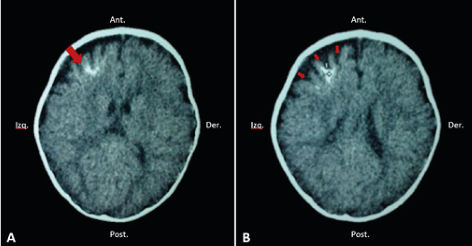

Se puede diagnosticar mediante el hallazgo de síntomas clínicos típicos y por la apariencia facial de la mácula en vino de Oporto 11. ?Todos los pacientes con nevus facial deben someterse a una evaluación radiológica para descartar SSW?, esta evaluación puede ser de ayuda para detectar las calcificaciones intracraneales clásicas de estos pacientes 1 ( Figura 2).

Fuente:elaboración propia.

Se han visto sin embargo múltiples hallazgos radiológicos como ser atrofia de lóbulos cerebrales, hipertrofia de plexos coroideos, agrandamiento de las venas cerebrales profundas, anomalías de drenaje venoso y recientemente se ha descrito un agrandamiento asimétrico del seno cavernoso 4, 24 ( Figura 3).